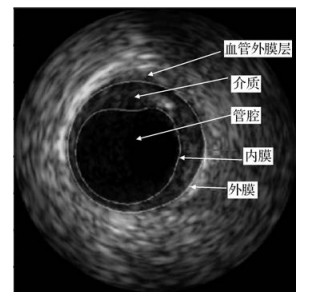

• 结合极值区域检测的血管内超声图像并行分割

叶红梅, 汪友生, 夏章涛, 刘继荣

2020, 25(2): 380-392. DOI: 10.11834/jig.190213

结合极值区域检测的血管内超声图像并行分割

摘要:目的血管内超声(IVUS)图像动脉壁边界分割不仅对血管壁和斑块特征的定量分析至关重要,而且对血管弹性定性分析和重建动脉3维模型也是必需的。针对IVUS图像传统分割方法建模复杂、运算量大且需分别设计算法串行提取内膜和外膜的缺点,本文提出基于极值区域检测的IVUS图像并行分割方法。方法本文方法包含极值区域检测、极值区域筛选以及轮廓拟合3部分。对单帧IVUS图像提取极值区域,经面积筛选后得到候选区域,并将区域的局部二值模式(LBP)特征、灰度差异和边缘周长的乘积作为筛选矢量在候选区域中提取代表管腔和介质的两个极值区域,并进行轮廓的椭圆拟合化,完成分割。结果在包含326幅20 MHz的IVUS(intravascular ultrasound)B模式图像的标准公开数据集上,定性展示极值区域轮廓和椭圆拟合轮廓,并与专家手动绘制的结果进行对比;然后使用DC(dice coefficient)、JI(jaccard index)、PAD(percentage of area difference)指标以及HD(hausdorff distance)对本文算法做鲁棒性测试和泛化测试,实验中内膜各指标值分别为0.94±0.02,0.90±0.04,0.05±0.05,0.28±0.14 mm,外膜各指标值分别为0.91±0.07,0.87±0.11,0.11±0.11,0.41±0.31 mm,与相关文献的定量对比实验结果表明本文算法提取的内外膜性能均有所提高。此外,本文方法在临床数据集上的测试效果也很好,与专家手动描绘十分接近。结论结合极值区域检测的IVUS图像并行分割,算法在精度和鲁棒性方面均得到了改善。

关键词:IVUS图像;内外膜分割;边缘检测;极值区域;轮廓拟合